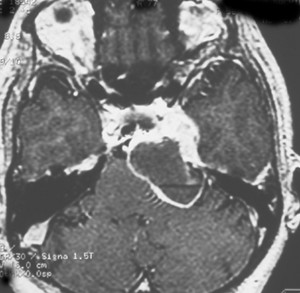

この腫瘍もちょっと大きいので放射線治療だけで治すことは難しいでしょう。この三叉神経鞘腫は少し大きいかなと思うくらいの大きさです。 脳幹部が圧迫されていますから手術摘出した方がいい例です。これも側頭部の前の方の骨を開頭するだけで全部取れます。